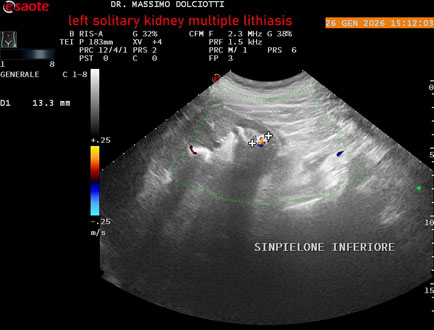

Data inserimento: 29/01/2026

Ecografia del: 26/01/2025

Strumento: Esaote MyLab Eight

Sonda: Conevx Multifrequenza 1-8 MHz

Età Paziente: M 78 anni

Motivazione dell'esame: follow up di litiasi al rene sinistro, in paziente sottoposto a nefrectomia destra.

Commento all'esame: le immagini ed il video documentano il rene sinistro in sede, di ecostruttura disomogenea per evidenza di multiple formazioni litiasiche al pielone superiore, delle dimensioni di 15,9 mm, al pielone medio di 17,5 mm e al pielone inferiore di 18,9 mm e morfovolumetria normale, con diametro bipolare di 115 (v.n. 90-120 mm) x 54 mm e parenchima renale dello spessore di 17 mm ( v.n. > 13 mm).

Conclusioni: litiasi multipla del monorene sinistro (multiple lithiasis of the left solitary kidney).

In collaborazione: Dr.ssa Marica Manfredi - Ancona, Dr. Ilir Qose - Ancona

Presentazione: Dr. Massimo Dolciotti - Ancona

Elaborazione digitale: Andrea Dini - Ancona